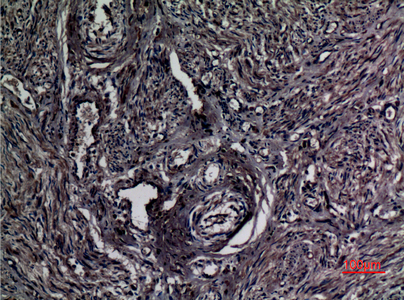

分类: 科研抗体货号: P23531别名: THBS2; TSP2; Thrombospondin-2应用: WB,IHC反应种属: Human,Mouse,Rat